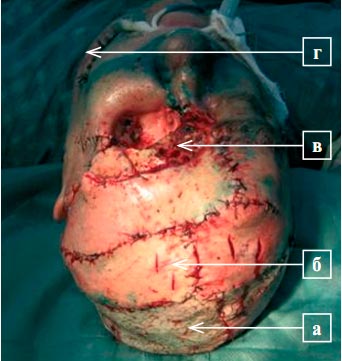

Малецкий А.П.

Резюме. Восстановление анатомических структур лица в связи с врожденными и приобретенными дефектами не всегда удается путем перемещения местных мягких тканей или использования аутотрансплантата кожи на сосудистой ножке. В работе представлены два клинических случая, в которых для закрытия дефектов мягких тканей и формирования век был применен разработанный более 100 лет тому назад Филатовым В. П. метод круглого шагающего стебля (филатовский стебель). Полученные результаты свидетельствуют об эффективности данной методики для решения сложных вопросов пластической и заместительной хирургии в офтальмологии.

Ключевые слова: реконструктивная хирургия, круглый шагающий стебель (филатовский стебель), онкология.